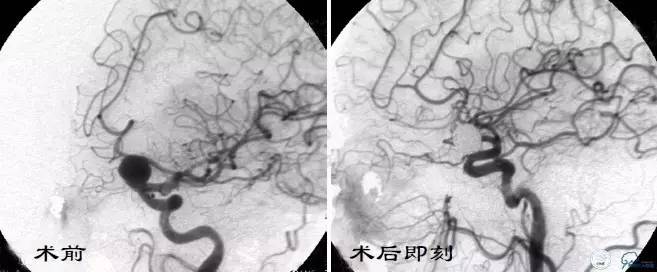

Case4 左ICA床突旁动脉瘤栓塞术后出血

术前VS术后即刻